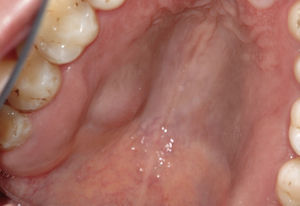

Papiloma de células escamosasSi bien en la bibliografía más reciente se insiste reitera-damente en que el papiloma de células escamosas y la verruga vulgar son clínicamente indistintos se ha optado por exponerlos de forma separada en el presente trabajo de revisión. El papiloma de células escamosas muestra un pico de incidencia entre la tercera y la quinta década de la vida. Suele tratarse de una lesión solitaria de crecimiento relativamente rápido hasta alcanzar un diámetro de 1–5 mm7. Los papilomas de células escamosas orales suelen tener una consistencia blanda y a menudo son pediculados. Son exofíticos en forma de coliflor con pro-longaciones blanquecinas y una superficie papilar a ve-rrugosa. Se localizan sobre todo en el paladar blando, la lengua, el frenillo lingual y el labio inferior7 (figs. 1–3, fig. 4a, fig. 4b, fig. 4c, fig. 4d, fig. 4e). Los VPH tipo 6 y 11 desempeñan un papel importante en estos tumores desde el punto de vista etiopatogénico7,18.

Dos terceras partes de los tumores de las glándulas salivales menores afectan a mujeres y una tercera parte a hombres. Estos tumores pueden aparecer en cualquier etapa de la vida, pero la edad media en el momento de la aparición se sitúa entre los 40 y los 60 años. La localización más frecuente es el paladar duro en su tercio posterior, seguido del paladar blando y de la mucosa del labio inferior. Sin embargo, pueden aparecer también en la mucosa yugal y en el trígono retromolar13. Por regla general, la sintomatología clínica no es llamativa y, con frecuencia, sólo se observa una ligera tumefacción que es indolora a la palpación. Además, los tumores de las glándulas salivales menores se caracterizan por un creci-miento lento y se manifiestan en forma de nódulos tisu-lares duros, desplazables, situados debajo de la mucosa intacta. Se pueden observar también pequeñas tramas vasculares sobre el tumor o en los márgenes del mismo.